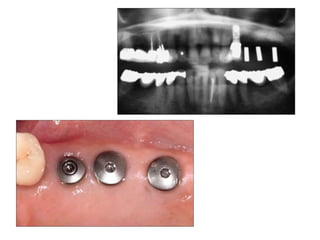

Implants require more precise impressions than crowns and bridges because implants lack a periodontal ligament to compensate for inaccuracies. It is critical to accurately record the three-dimensional position, angulation, and depth of implants to obtain a proper fitting definitive restoration. Making high quality impressions at the implant or abutment level is necessary to successfully fabricate implant prostheses.